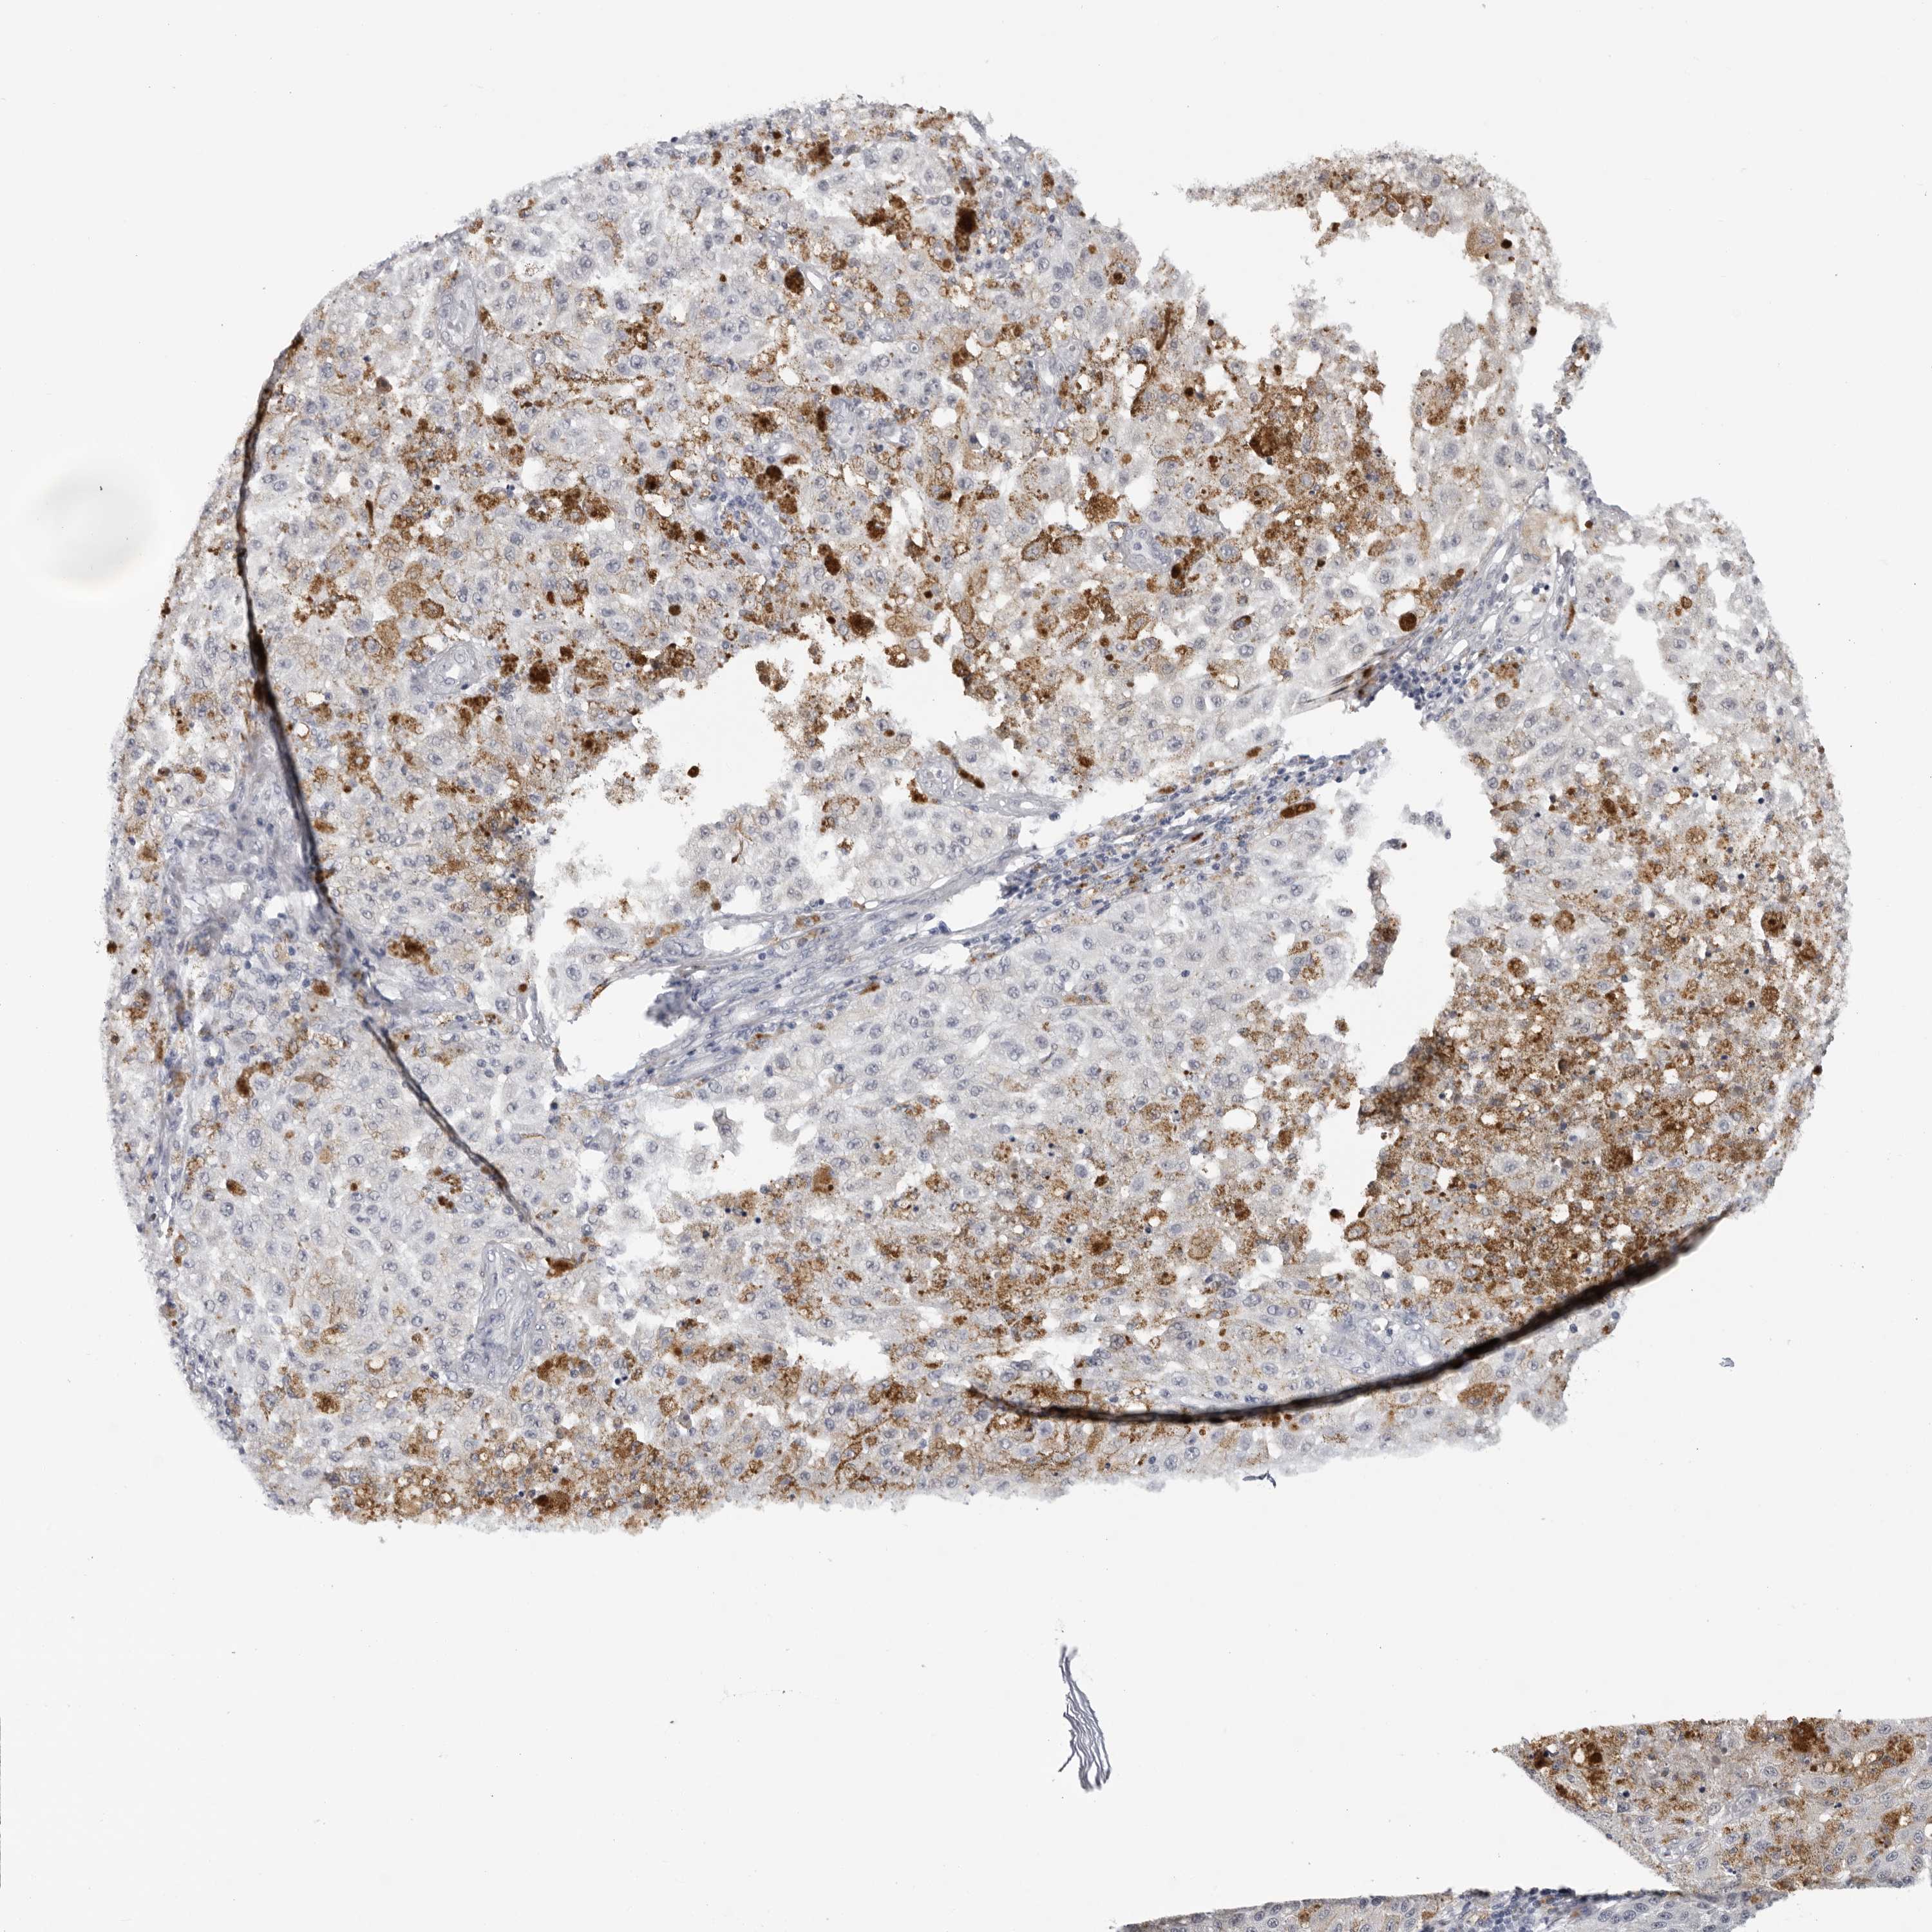

MELANOMA - Protein expressioni

A mouse-over function shows sample information and annotation data. Click on an image to view it in a full screen mode. Samples can be filtered based on level of antibody staining by selecting one or several of the following categories: high, medium, low and not detected. The assay and annotation is described here.

Note that samples used for immunohistochemistry by the Human Protein Atlas do not correspond to samples in the TCGA dataset.

Antibody stainingi

Antibody staining in the annotated cell types in the current human tissue is reported as not detected, low, medium, or high, based on conventional immunohistochemistry profiling in selected tissues. This score is based on the combination of the staining intensity and fraction of stained cells.

Each image is clickable and will lead to virtual microscopy that enables deeper exploration of all samples and also displays staining intensity scores, fraction scores and subcellular localization as well as patient and tissue information for each sample.

Antibody HPA024761

Antibody HPA029557

Staining

High

Medium

Low

Not detected

Intensity

Strong

Moderate

Weak

Negative

Quantity

>75%

75%-25%

<25%

None

Location

Nuclear

Cytoplasmic/membranous

Cytoplasmic/membranous,nuclear

Malignant melanoma, NOS

Malignant melanoma, Metastatic site